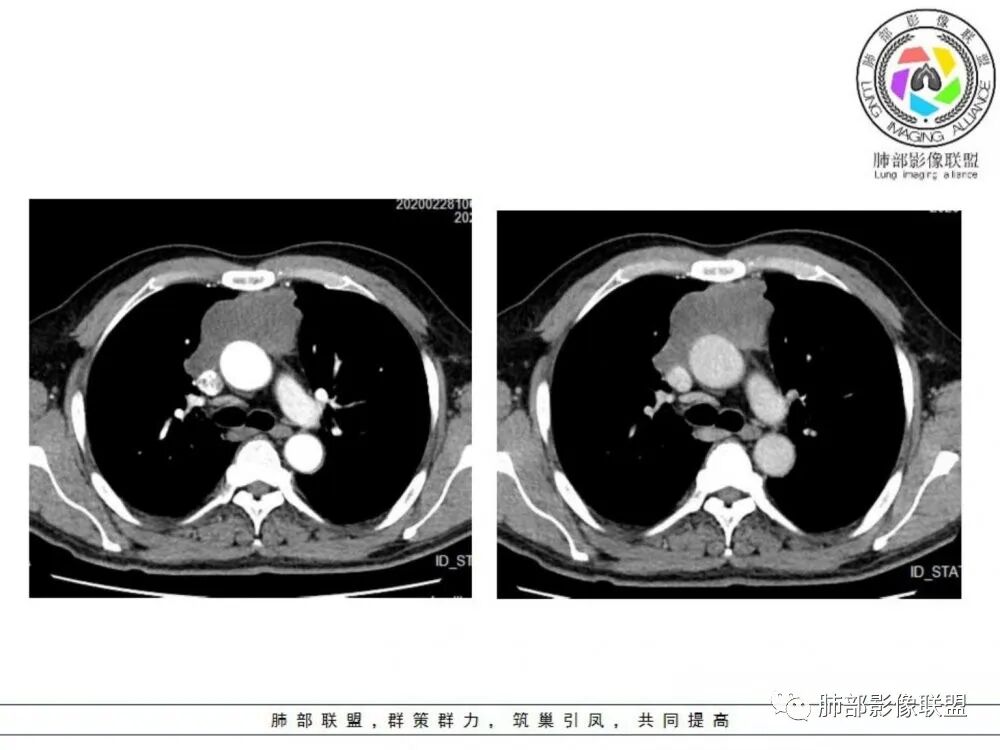

男性患者,65岁,前胸后背疼痛一个月。影像学前上纵隔分叶状的软组织肿块,肿块形态怪异,偏软,位于大血管间隙前,并有向血管后间隙发展的趋势,平扫CT值为40左右,增强扫描中心部未见强化,周围轻度的强化,约为50左右。前上纵隔的疾病谱包抬胸廓内甲状腺肿、胸腺瘤/癌、畸胎瘤、淋巴瘤。少见的心包囊肿或支气管囊肿。根据肿块的形态及强化特点,首先还是排除了胸内甲状腺肿及胸腺来源的肿物,这类的肿物强化比较明显。畸胎瘤成分比较复杂,具有软组织钙化或者脂肪类的组织,这个肿物虽然在平扫的时候好像有斑点状的钙化灶,但是总体成分还是比较单一,所以还是排除畸胎瘤的诊断。所以这样的情况是考虑:淋巴类的肿瘤,注意排除心包的囊肿或支气管来源的囊肿。

老年男性患者,前膈软组织肿块,边缘轮廓不光整,边界似乎尚清晰,内见小点状钙化灶,平扫密度欠均匀,增强后轻度强化表现,边缘有些斑片状的高强化区。综合考虑胸腺瘤或胸腺鳞癌,神经内分泌癌强化弱了一些。患者年龄较大,生殖细胞肿瘤不考虑,淋巴瘤血管包绕不够,可能性不大

老年男性,前胸后背痛一个月,前纵隔不规则肿块,分叶,向纵隔血管间隙进入,且与纵隔血管分界不清,增强边缘轻度强化,中间可见无强化区,似见点状钙化,PET为高代谢,考虑为来源于胸腺,胸腺瘤或胸腺鳞癌可能

临床,老年男性,病史一月。1 定位,骑跨大血管,大部分位于胸腺区域内,周边部分胸腺脂肪有混浑浊,起源于胸腺区的组织应该没有问题。2 定性 。恶性征像,分叶,大血管侵润,pet高代谢,左侧庄层胸膜增厚(类似脑膜瘤的脑膜尾征,良性表现?)。良性征像,病灶均匀,无明确坏死?综合恶性征像多些,考虑恶性可能大。病灶分两部分,部分层面似有明确分割,两个性质的病灶长一块,还是,一个病灶两种不同成分?一个病灶伴均匀坏死?CT值41hu,坏死好像高了点,一个病灶,相同成分,只是血管分布不同,增强是持续流入型强化。纤维类?编不下去了,岔路太多,祭出法宝按概率蒙吧:侵袭性胸腺瘤>神经纤维瘤>乏血供CD

老年男性,定位前纵隔,似乎有点塑形生长,肿块与大血管分界欠清,上腔静脉局部包绕受压,侵犯?增强扫描低强化。考虑恶性,胸腺癌可能。鉴别淋巴瘤。

老年男性患者,前膈软组织肿块,边界似乎尚清晰,内见小点状钙化灶,平扫密度欠均匀,增强后轻度强化表现,边缘有些斑片状的高强化区,考虑胸腺瘤或胸腺癌。

前纵隔不规则肿块,分叶,与纵隔大血管脂肪界面消失,轻度不均匀强化,未见纤维分隔,考虑胸腺癌或胸腺瘤,鉴别淋巴瘤

中老年男性,前纵隔占位,基本居中,向两侧生长;边缘膨隆分叶,部分边界不清,增强不均匀轻中度强化,坏死区边界不清;周围多发增大淋巴结,考虑恶性。主要在胸腺癌、胸腺瘤、淋巴瘤之间鉴别。病灶偏软,有钻缝样生长,这些征象偏向于淋巴瘤。但此例老年患者,病灶内有点状钙化,缺乏结节堆砌感,倾向胸腺癌诊断。